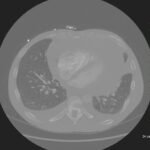

Cardiac tamponade is a rare and life-threatening condition that can be caused by trauma and various medical conditions. Failure to recognize and repair it quickly could lead to significant morbidity or even death. This case demonstrates the electrocardiogram (ECG) findings of low voltage QRS and electrical alternans in cardiac tamponade. It also highlights the classic ultrasound (US) findings of pericardial effusion and right ventricular collapse during diastole in cardiac tamponade. Classic physical exam findings of cardiac tamponade include Beck’s Triad (jugular venous distention, hypotension, and muffled heart sounds) and pulsus paradoxus. This patient only had jugular venous distention and pulsus paradoxus. The case is centered on a 52-year-old male who presented with shortness of breath, wheezing, and a productive cough with streaks of blood. A CT chest was performed which revealed a large pericardial effusion, right upper lobe lung mass, and bilateral pulmonary emboli. A bedside transthoracic echocardiogram was then performed which confirmed the large effusion as well as right ventricular collapse during diastole. Cardiothoracic surgery and interventional cardiology were consulted and both agreed to take the patient to the cardiac catheterization lab for percutaneous drainage of the effusion. Pericardiocentesis was performed and 1.7 liters of serosanguinous fluid was removed and a drain was left in place. He recovered well from the procedure and had an uneventful admission. After reviewing this case, learners should be able to recognize the diagnostic features and various causes of pericardial effusion and cardiac tamponade.